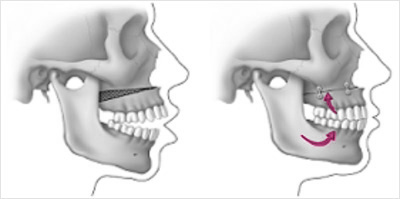

Correcting an open occlusion is done by means of surgery to the upper jaw and sometimes to the lower jaw also, to allow the back teeth to chew together.